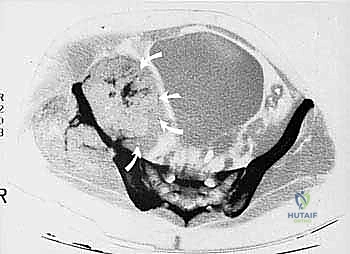

* CT with Intravenous Contrast and 3D Reconstruction (FIG 3): This is our workhorse for assessing bone involvement, destruction, and the critical relationship between the tumor and major pelvic blood vessels. It reveals any distortion of the pelvic anatomy and guides resectability. Figure 3A clearly shows extensive bone destruction and tumor extension into the pelvis and gluteal region. Figure 3C highlights an extensive tumor on the medial aspect of the ilium with destruction of the inner table.